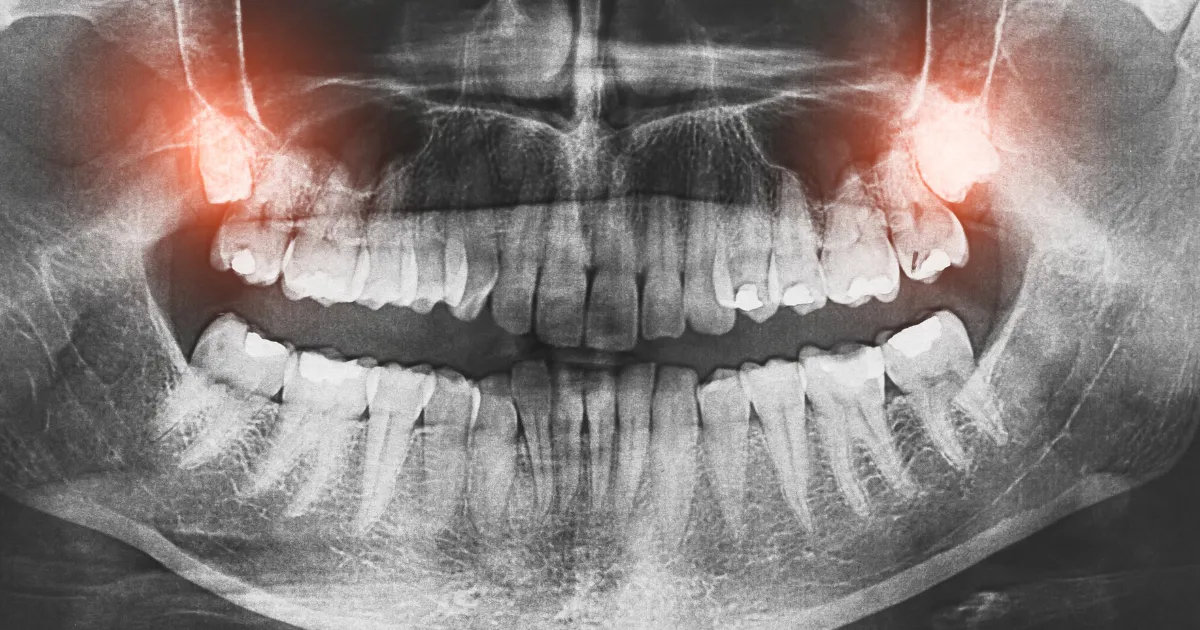

口腔内診査はもちろんのこと、X線撮影やCTスキャンを用いて、親知らずの位置や状態を詳細に調べます。

これにより抜歯が必要かどうか、またその難易度を判断します。

検査結果を基に、どのタイミングで抜歯を行うか、抜歯の難易度やリスクについて説明します。